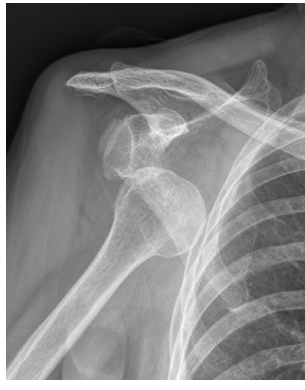

급성 탈구인 경우 진찰소견과 엑스레이 소견을 보고 탈구의 방향을 조사하는데 대부분의 경우 팔이 앞쪽으로 빠지는 전방 탈구입니다. 재발성 탈구가 되면 MRI 등으로 관절순 또는 인대들의 상태를 분석하는 것이 필요합니다. 또한 재발성 탈구시 골절을 동반하는 경우와 골결손이 심하면 수술전 CT사진이 필요합니다.